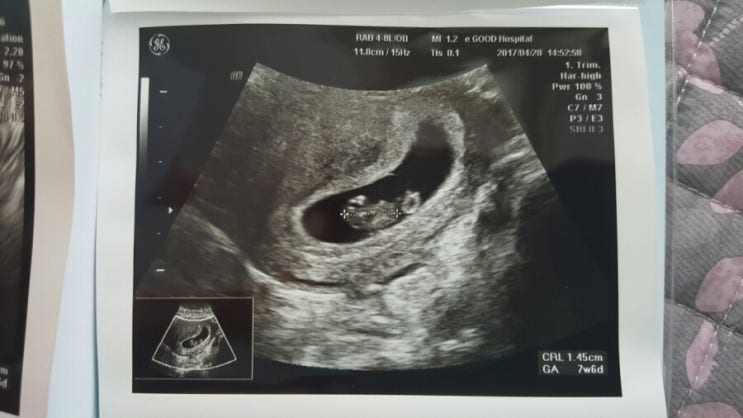

임신 8주 증상 / 임신 초기 짜증 / 입덧 물러가라 / 배초음파 시작 / 임신 서적 구매

저번 주 금요일날(17.4.28.임신8주째) 병원을 다녀왔는데 입덧하고 그러다보니 블로그고 나발이고 내 몸이 ...